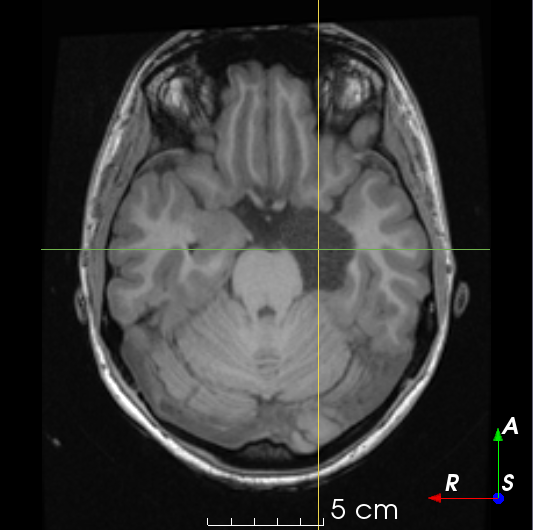

2.2 Dataset Description

T1𝑇1T1-weighted MR images were collected from publicly available datasets Information eXtraction from Images (IXI) (566), Alzheimer’s Disease Neuroimaging Initiative (ADNI) (467), and Open Access Series of Imaging Studies (OASIS) (780), for a total of 1813 images. EPISURG was obtained from patients with refractory focal epilepsy who underwent resective surgery at the National Hospital for Neurology and Neurosurgery (NHNN), London, United Kingdom. This was an analysis of anonymized data that had been previously acquired as a part of clinical care, so individual patient consent was not required. In total there were 431 patients with postoperative T1subscript𝑇1T_{1}-weighted MR images, 269 of which had a corresponding preoperative MR image. All images were registered to a common template space using NiftyReg [17].